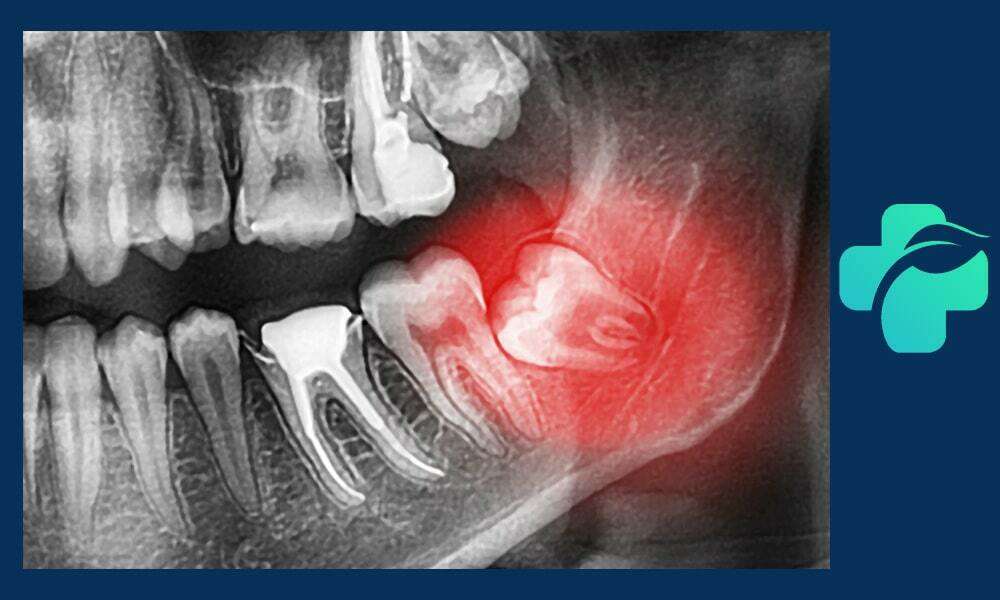

معمولاً پزشک با بررسی عکس پرتوی ایکس، بهترین روش درمان جراحی دندان عقل نهفته را انتخاب می کند.

گاهی این دندان ها به دلیل نداشتن فضای کافی یا رشد نادرست، دندان عقل نهفته می شوند؛ یعنی به طور کامل یا جزئی از لثه بیرون نزده اند. این وضعیت باعث درد، عفونت، التهاب و حتی آسیب به دندان های مجاور می شود که در این شرایط جراحی دندان عقل ضروری است. اقدام به موقع برای جراحی کشیدن دندان عقل نهفته درد و مشکلات بعدی را به حداقل می رساند.

جراحی دندان عقل پیچیده برای دندان هایی انجام می شود که در زاویه نامناسب، عمیق یا با ساختار استخوانی دشوار قرار دارند. این نوع جراحی نیاز به تخصص بالای جراح دهان و فک دارد و ممکن است شامل برش گسترده لثه، برداشت استخوان و تقسیم دندان به قطعات برای خارج کردن آن باشد. جراحی پیچیده معمولاً طولانی تر و همراه با تورم و درد بیشتری است و دوره نقاهت آن نیز طولانی تر است. رعایت دقیق مراقبت های پس از جراحی، از جمله استفاده از مسکن ها، یخ گذاری، رژیم غذایی نرم و رعایت بهداشت دهان، برای جلوگیری از عفونت و بهبود سریع بسیار اهمیت دارد. این نوع جراحی معمولاً برای دندان هایی که رشد کامل ندارند یا زاویه آن ها نامناسب است ضروری است.

چه زمانی جراحی دندان عقل ضروری است؟

همه دندان های عقل نیاز به جراحی ندارند. اما در شرایط زیر جراحی دندان عقل نهفته یا نیمه نهفته ضروری می شود:

- ایجاد کیست یا آبسه

- آسیب به دندان های مجاور

- فشار به سایر دندان ها و ایجاد نامرتبی